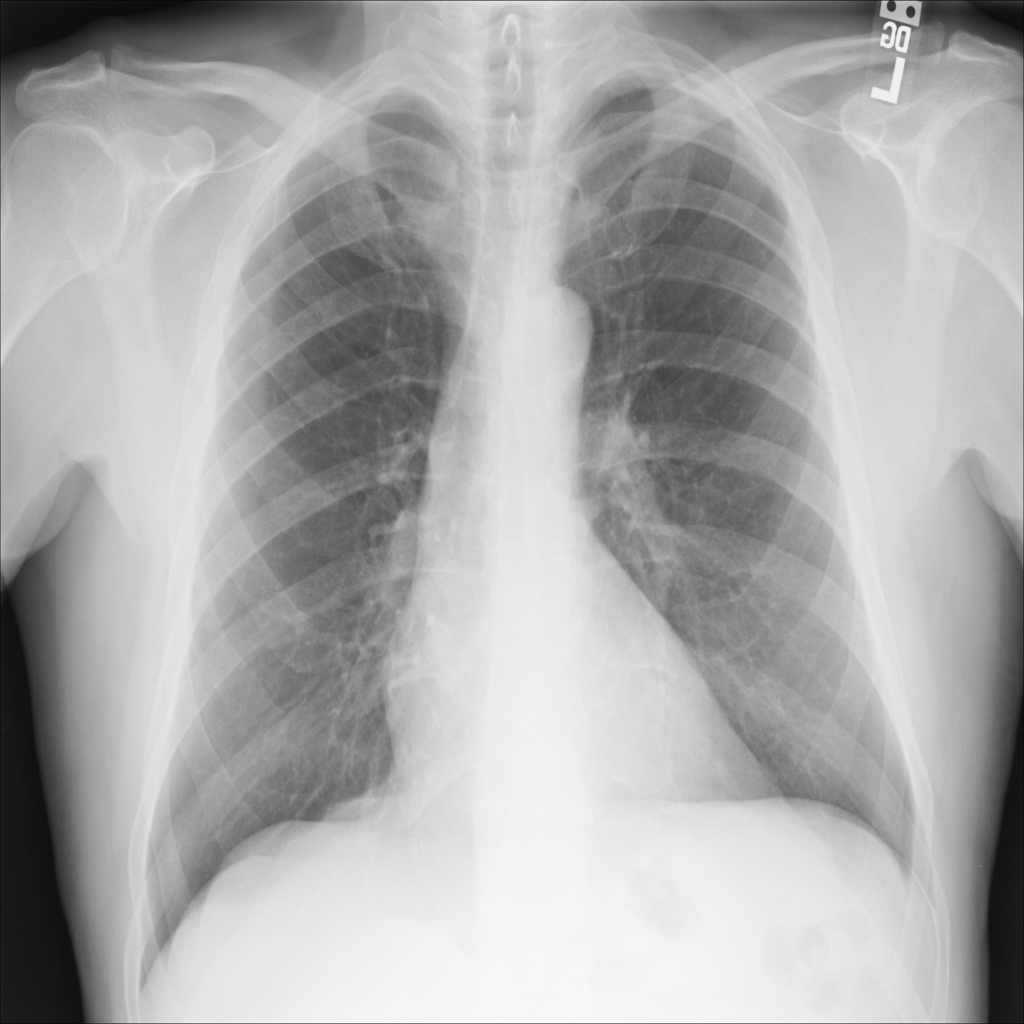

PAT-C255 · IMG-000Emphysema

PAT-C255 · IMG-000

PA